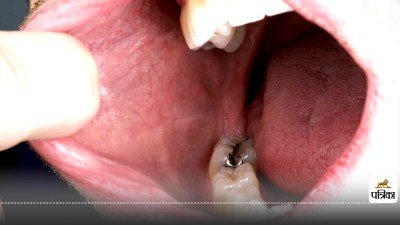

चौंकाने वाला खुलासा: Oral cancer के पीछे ये है सबसे बड़ी वजह

Oral cancer causes : भारत में मुंह का कैंसर तेजी से बाद रहा है। लेकिन इसकी बड़ी वजह धूम्रपान नहीं बल्कि अत्यधिक मीठे पेय पदार्थों का सेवन है। जो महिलाएं रोजाना कम से कम एक शुगर-स्वीटेंड ड्रिंक (मीठा पेय) पीती हैं, उनमें मुंह के कैंसर (Muh ka cancer) का खतरा लगभग 5 गुना बढ़ जाता है।

Oral cancer causes : वॉशिंगटन विश्वविद्यालय द्वारा हाल ही में प्रकाशित एक अध्ययन में यह चौंकाने वाला खुलासा हुआ है कि जो महिलाएं रोज़ाना कम से कम एक शुगर-स्वीटेंड ड्रिंक (मीठा पेय) पीती हैं, उनमें मुंह के कैंसर (Muh ka cancer) का खतरा लगभग 5 गुना बढ़ जाता है। यह शोध "JAMA Otolaryngology-Head & Neck Surgery" में प्रकाशित हुआ है और स्वास्थ्य विशेषज्ञों को नए सिरे से सोचने पर मजबूर कर रहा है।